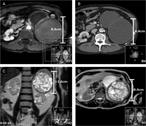

Resection of a mature cystic teratoma of the liver harboring a carcinoid tumor

Alexei A Krainev and others

Journal of Surgical Case Reports, Volume 2018, Issue 10, October 2018, rjy279, https://doi.org/10.1093/jscr/rjy279